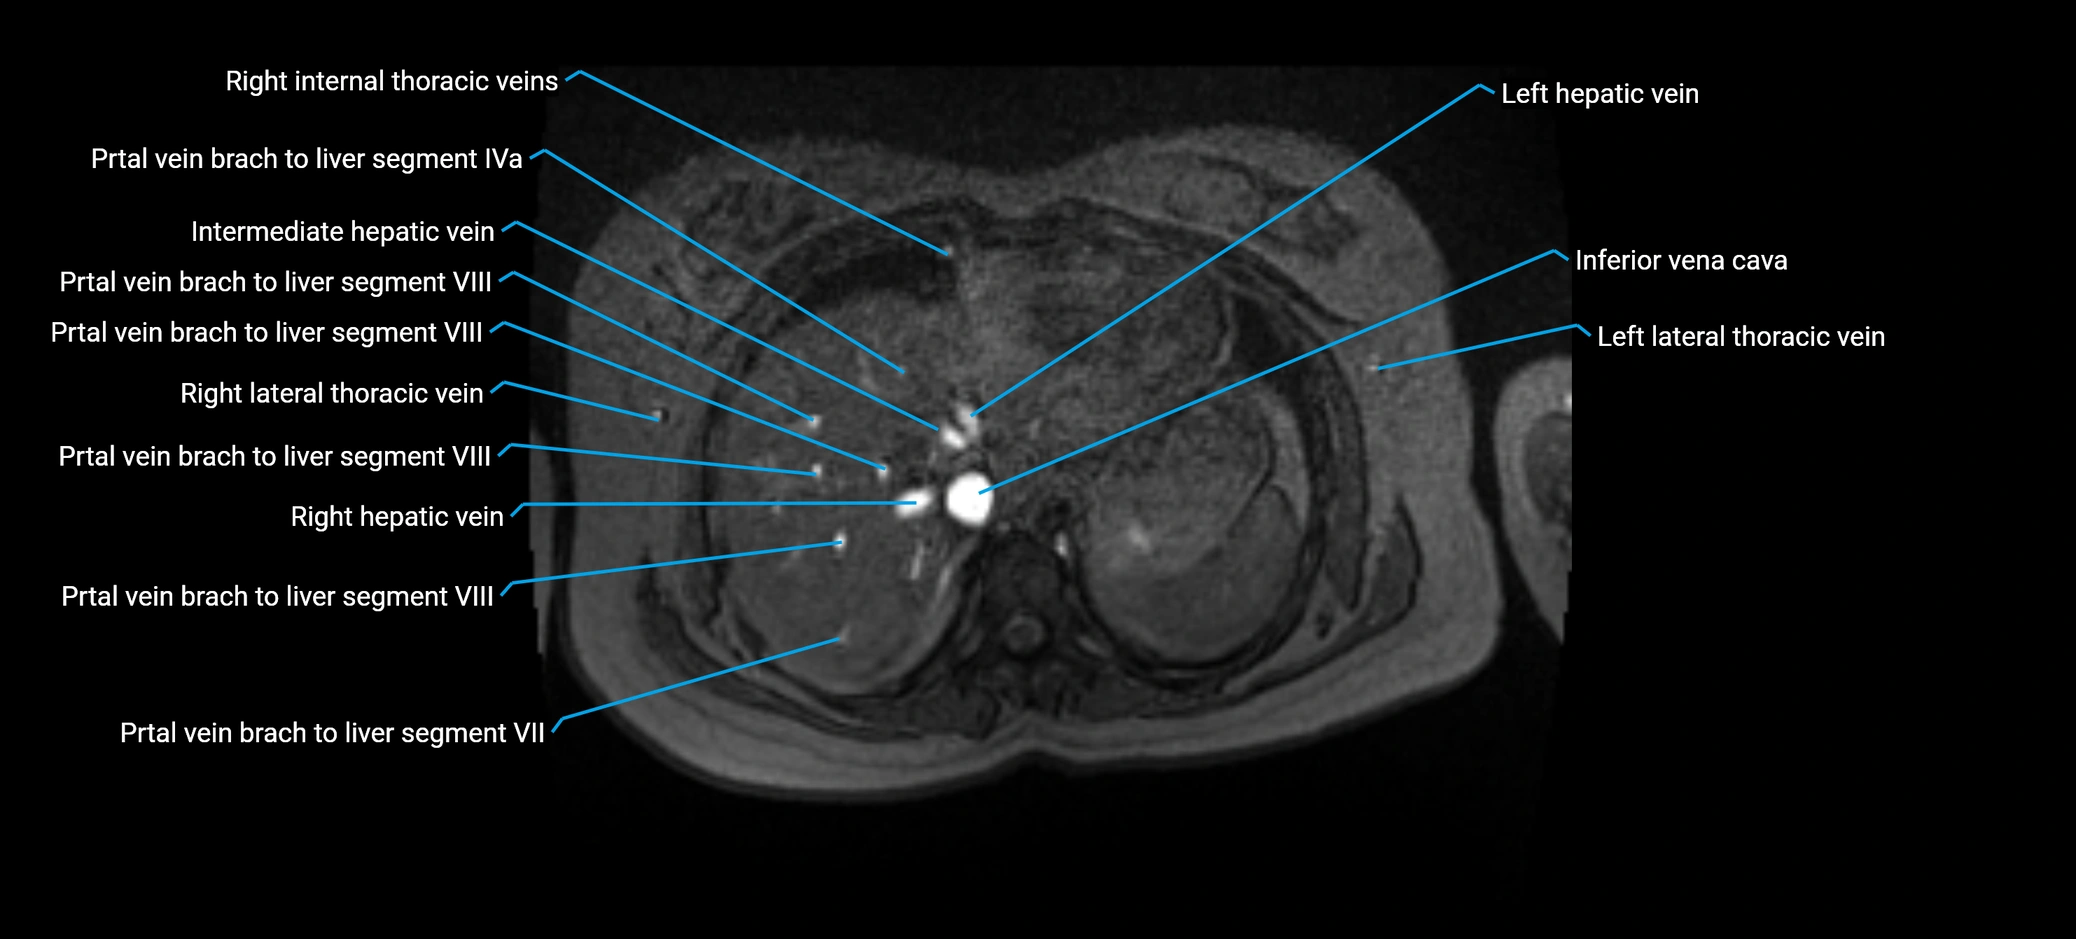

MRV TOF (Time-of-Flight MR Venography):

• Appears as a bright, high-signal vascular channel representing flowing blood

• Clearly shows branching pattern of right portal vein into anterior and posterior branches

• Best in coronal or axial reconstructions for segmental mapping

• No need for contrast, relies on flow-related enhancement

MRI image

image